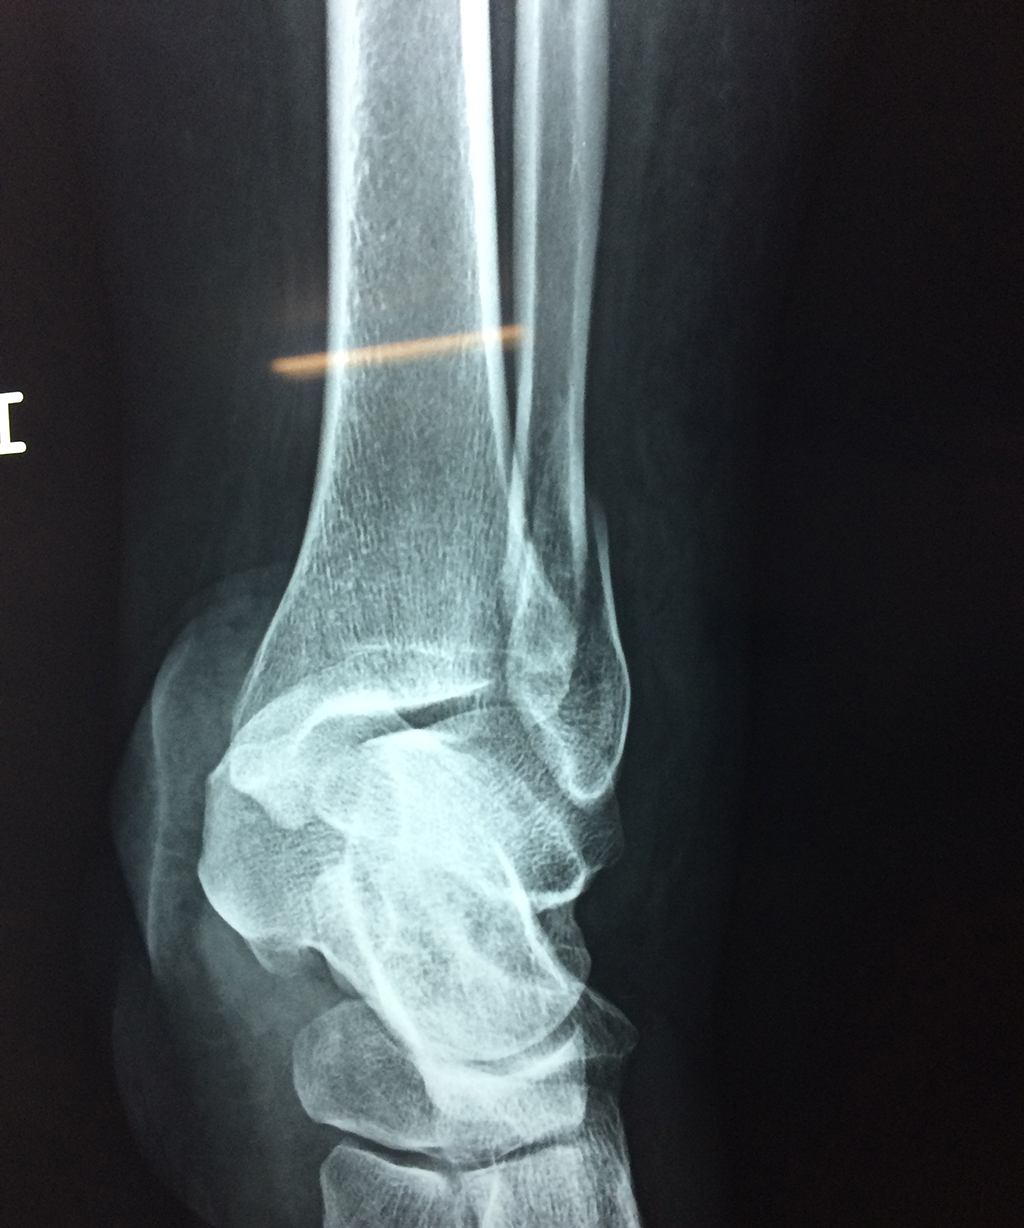

Algunas fracturas de tobillo pueden requerir cirugía si:

- Los extremos de los huesos están desalineados entre sí (desplazados).

- La fractura se extiende hasta la articulación del tobillo (fractura intra-articular).

- Los tendones o ligamentos (tejidos que sujetan los músculos y los huesos entre sí) están rotos.

Cuando se necesita cirugía, es probable que esta implique el uso de clavijas de metal, tornillos o placas para sostener los huesos en su lugar mientras la fractura se consolida. Los elementos de soporte pueden ser temporales o permanentes.